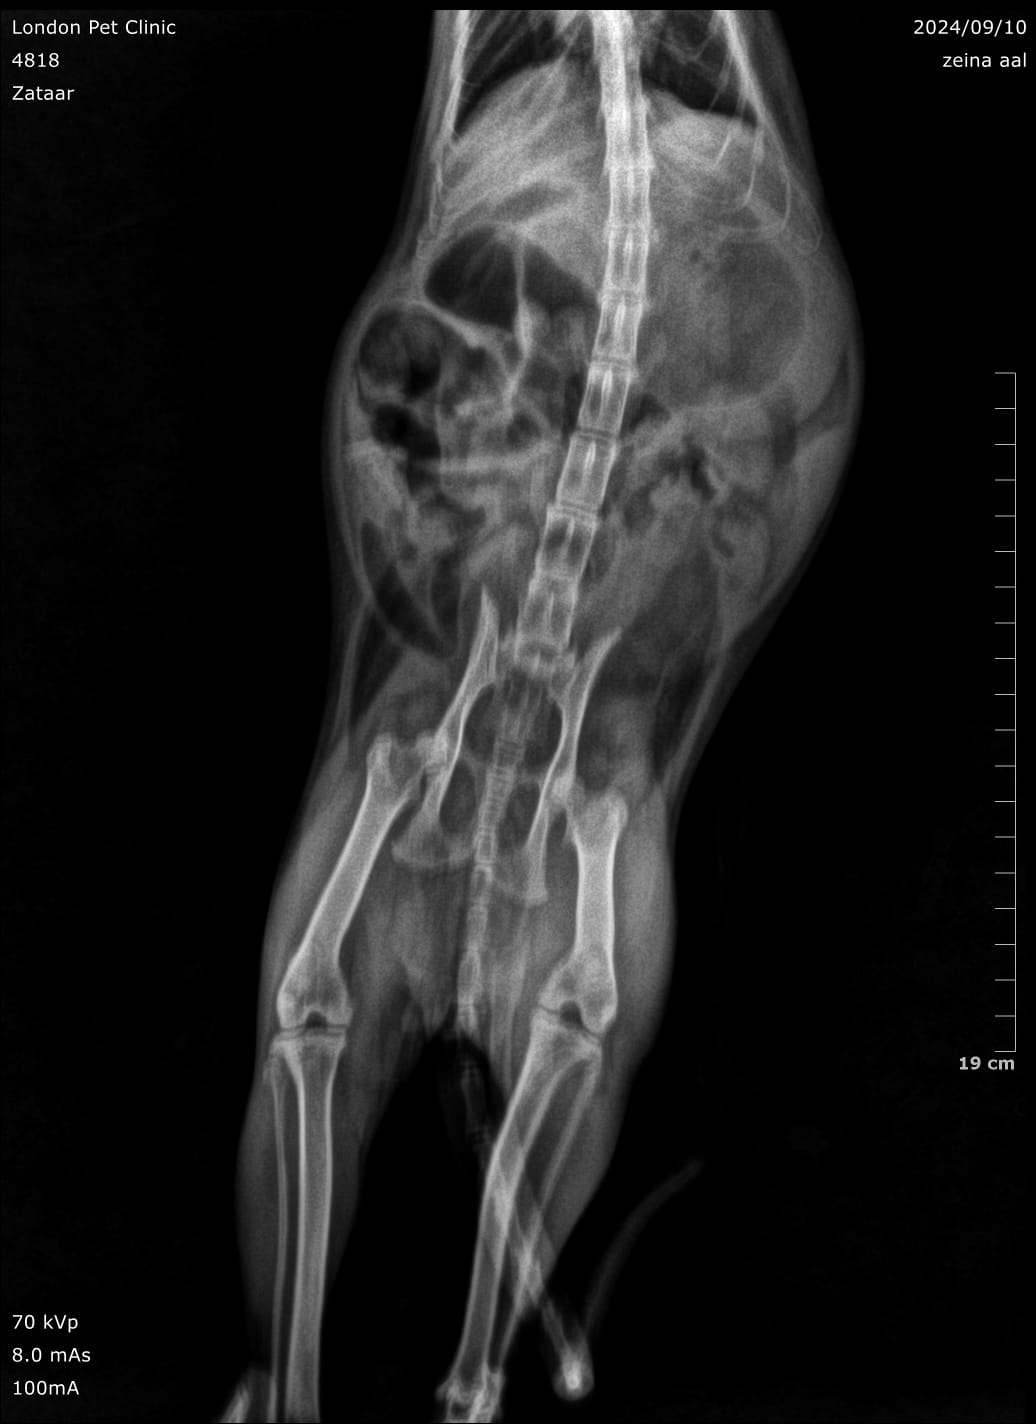

Abdominal radiographs: May show a gas--distended stomach with clogging clump

Abdominal ultrasound: was consistent of GOO due to hairball with fluid accumulation in the stomach

Trichobezoar causing chronic GIT signs in a 5 years old cat and lately more aggressive presentation

Large hairball lodged in the pyloric antrum

Post-Operative X ray